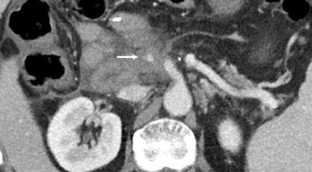

Fig. 3

Fig. 4